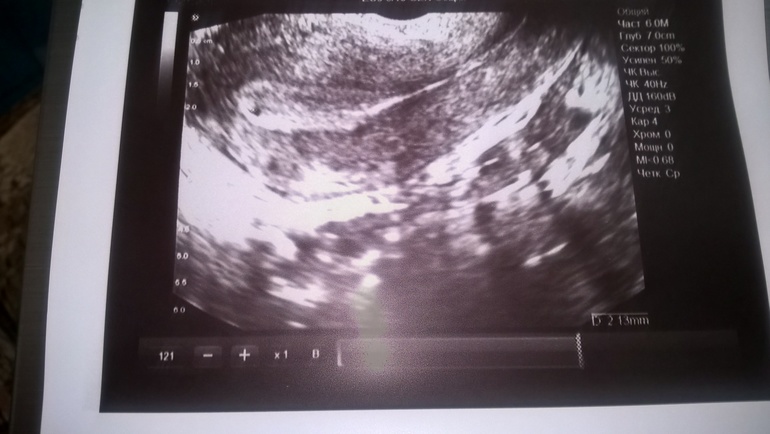

сходила я на узи и тоже ничего не понятно,только врач начал смотреть по животу,сразу сказал,что пришла рановато,и стал смотреть трансвагинально,смотрел-смотрел,потом повернул экран ко мне и показал картинку,сказал,мол вот видишь слева в матке точка черная,возможно она перерастет в беременность,еще пока рано говорить точно,но в матке что-то есть...сказал прийти через неделю....говорит иногда и с двухнедельной задержкой бывает не видно Б...